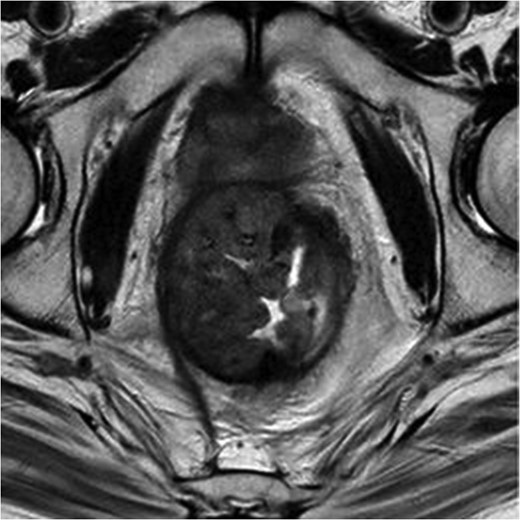

MRI pelvis. T2 axial image through pelvis demonstrating limited response to chemoradiotherapy with tumoral margins still predicted positive.